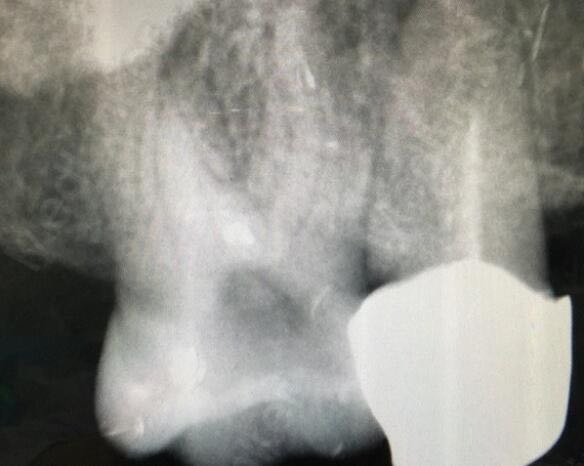

16牙可见腭侧龋坏,可探及穿髓孔,冷(+-)叩(+-)探(++) X线示龋洞近髓,牙周膜增宽影像

16牙慢性牙髓炎 根管治疗,四根管,近颊,mb2,远颊,腭,龋洞处开髓,开髓孔小,破坏牙体组织少